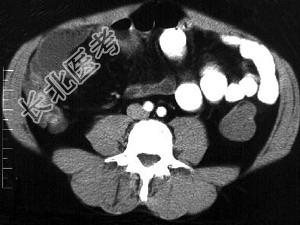

- 单项选择题女,30岁, 右下腹痛,腹泻便秘交替出现, 消瘦乏力,血沉加快, X线检查如图,最佳的诊断是 ( )

A、小肠癌

B、小肠结核

C、小肠克罗恩病

D、结肠癌

E、阑尾炎